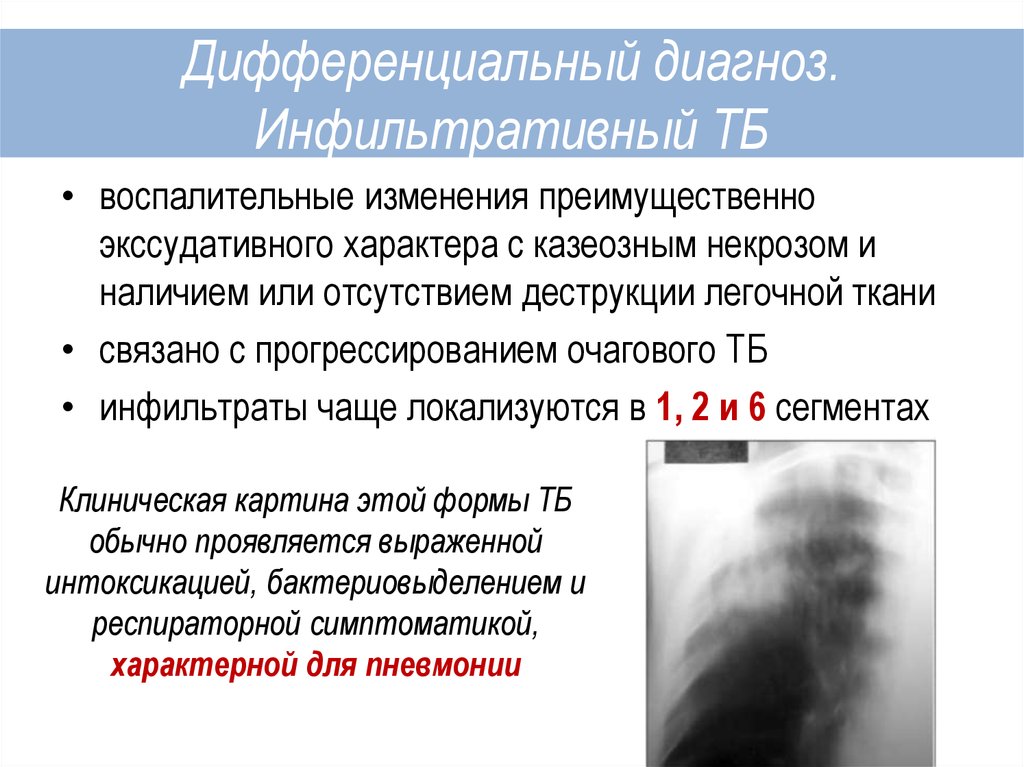

Бактериальная деструкция легких у детей презентация - 88 фото